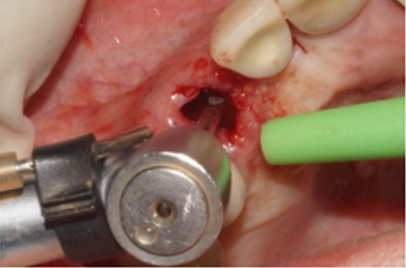

Figura 3 – Dispositivo para exodontia

Figura 5 – Fresagem do leito cirúrgico